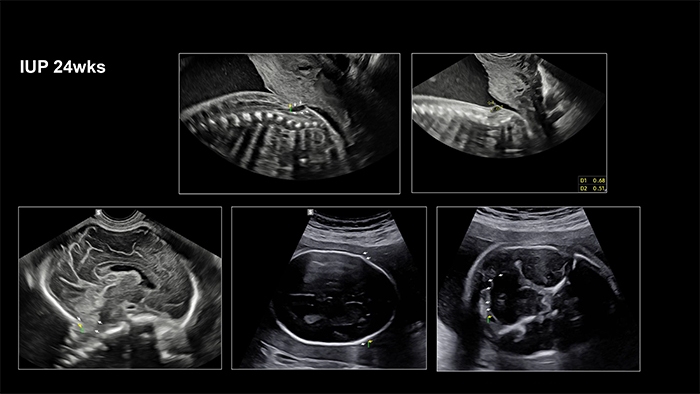

A 36-year-old woman, diagnosed with fetal myelomeningocele (mmc), visited outpatient clinic at 24 weeks and 0 days’ gestation. She said that everyone told me to give up the baby.

Chiari II malformation was suspected on ultrasonography and fetal MRI. However, sac size was small and fetal leg movements were active. A multidisciplinary counselling was performed. Although mmc of the fetus had been progressed slowly after 30 weeks’ gestation and mother received cesarean section at 35 weeks’gestation due to preterm labor, the neonate received immediate postnatal operation for mmc.